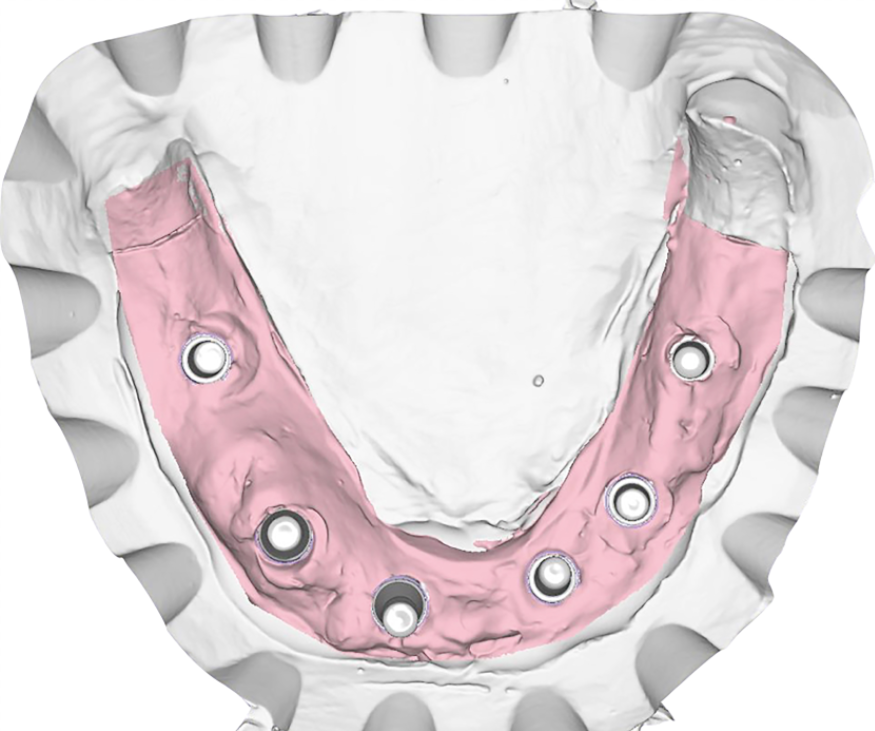

Dopo la rimozione dei denti residui e degli impianti, il paziente è stato immediatamente riabilitato con due protesi totali rimovibili diagnostiche in RP, che hanno migliorato i rapporti intermascellari, la VDO, OB, OJ, fonetica ed estetica. È stato eseguito un tracciato cefalometrico su una radiografia laterale del cranio per una valutazione funzionale iniziale del caso, seguita da una pianificazione protesica virtuale (Fig. 4), quindi radiologica (Fig. 5) e chirurgica. Le caratteristiche delle protesi studiate hanno determinato la pianificazione chirurgica (Smop, SwissMeda) (Fig. 6) e due guide chirurgiche sono state successivamente sinterizzate al laser (2Ingis) (Fig. 7). Gli impianti sono stati quindi posizionati come programmato (Figg. 8, 9), ad eccezione di quelli ai mascellari posteriori, dove è stato eseguito bilateralmente un grande rialzo del seno mascellare (Fig. 10).

Dopo due mesi è stata eseguita una scansione (Fig. 11) e i modelli in stampa 3D successivamente prodotti sono stati zoccolati per articolatore e ri-virtualizzati (Fig. 12) utilizzando un desktop scanner (inEos X5, Dentsply Sirona). I rapporti intermascellari e la posizione degli impianti sono stati accuratamente registrati, duplicando le protesi provvisorie in resina trasparente e fissando in bocca le posizioni dei transferts sui duplicati. La passività e precisione dei transferts in occlusione devono in questa fase essere controllate con estrema accuratezza. L’occlusione dei duplicati è usata quindi per il montaggio dei modelli zoccolati, che sono stati fissati su basi di montaggio con un arco facciale in un articolatore arcon completamente regolabile (Reference SL, Gamma Dental).